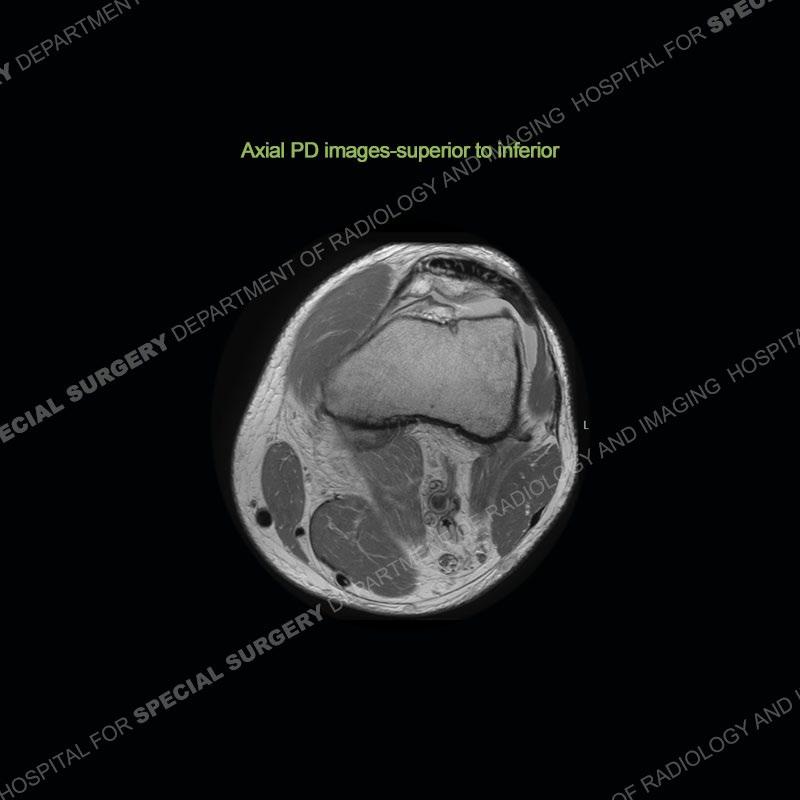

Findings

The radiographs show degenerative change of the medial compartment and a varus knee, but they are not germane to this case. No acute bony injury is present. The MRI shows edema of the posterior medial knee/soft tissue and a focal area of a partially disrupted low signal structure. The details are kept at a minimum in the findings of this case on purpose.

Diagnosis: Partial Disruption Medial Head Gastrocnemius (MHG)

The findings were kept purposefully vague as identifying the structures early on takes away a lot of the diagnosis. An uncommon entity and one of which we do not see a lot. Enthesopathic changes and tendinosis are seen as are distal MHG injuries, but proximal tears are rarely present. This case highlights a number of points. One, it almost always comes down to anatomy. Perhaps not a structure we normally spend too much time on, except save for diagnosing a Baker’s cyst, but knowing where this structure and all structures exist in all three planes is imperative. Second, when you think you are making a “call” or finding that you have never made before, step back and think is this just the abnormal presentation of a common pathology. That situation arises much more frequently. Third, if you look at it once, twice, and probably a third time and are confident in your odd or very rare diagnosis, stick to your guns. Especially, when it comes down to anatomic structures, the proof will be in the images.

Fourth, use all imaging planes and different pulse sequences to make your diagnosis. The edema highlighted in this case can be seen as the obscuration of fat on the PD images but is much easier to perceive as the high signal on the IR pulse sequences. The actual disruption of the MHG myotendinous junction is only able to be seen on the axial images. On the sagittal and coronal images, we get a sense something is wrong but hard to be exact. Lastly, when you look at a study and something just seems off (as I would say the sagittal and coronal images do with that dark band of tissue posteriorly), listen to yourself and go through the study slowly and meticulously. Most of the time you will find you were right, and something indeed is present.